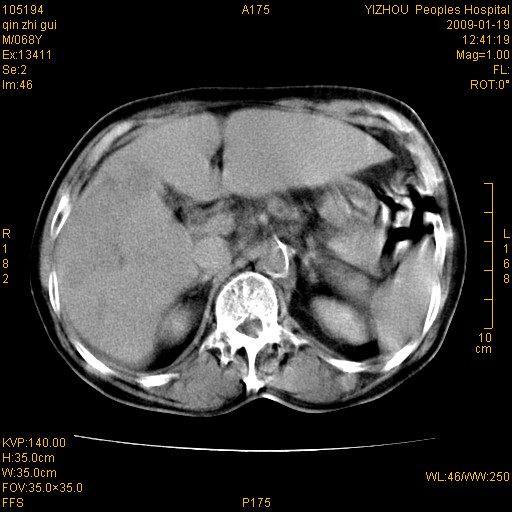

以下是引用随光逐影在2009-1-21 16:11:00的发言:[br]1)考虑肝右叶肝癌并肝静脉及门静脉瘤栓形成。2)肝硬化,少量腹水。3)胆囊炎。4)右侧少量胸腔积液。

病灶外缘凹凸不平,平扫低密度,增强动脉期有强化,门脉早显,静脉期及延期呈延迟强化,结合病史考虑右肝前叶巨块型肝癌可能性大,强化表现不除外胆管细胞癌